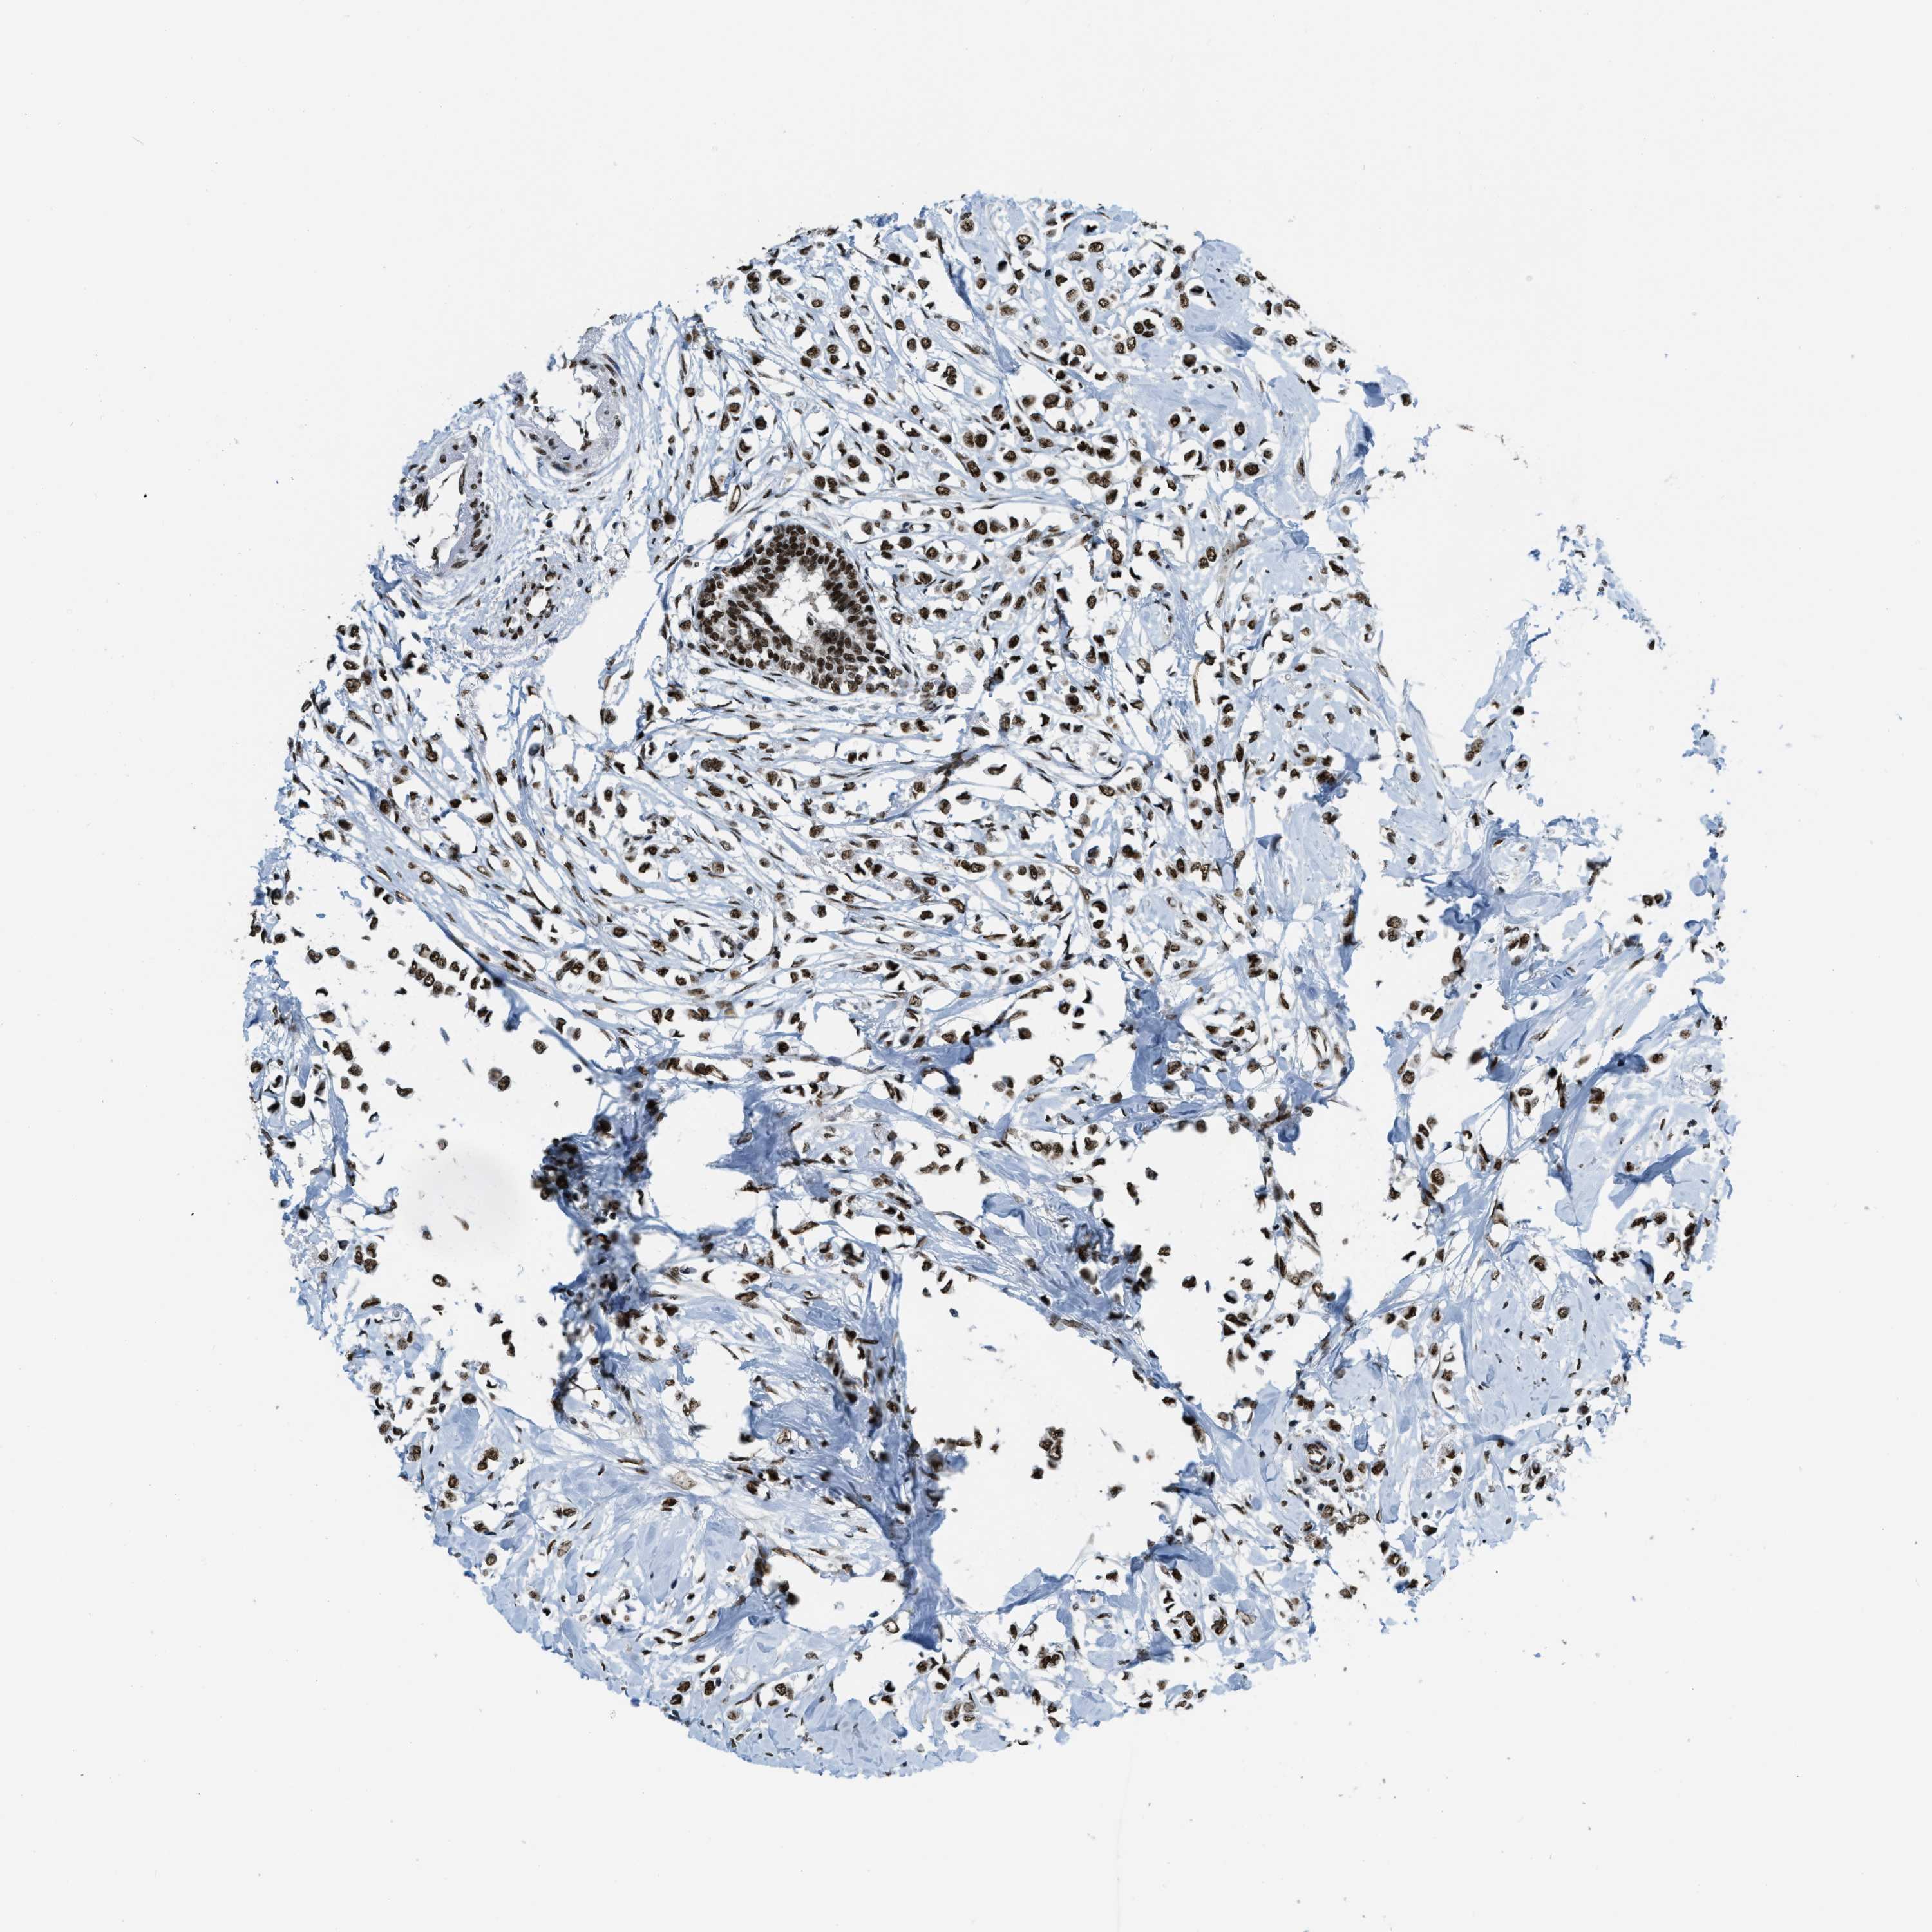

CANCER BREAST CANCER Show tissue menu

BRCA TCGA BRCA VALIDATION PROTEIN EXPRESSION

ANTIBODIES

AND

VALIDATION